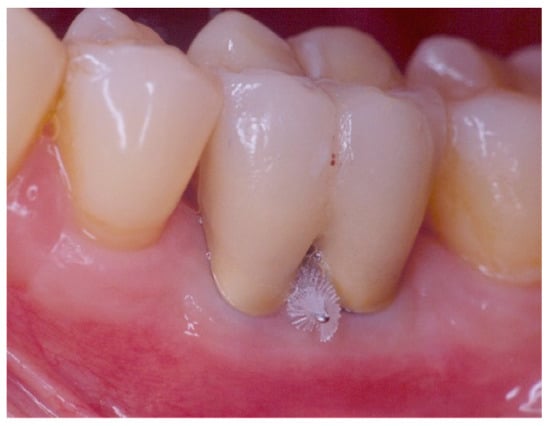

Figure 5. Non-exposed furcation lesion—Class III (NEIII): First mandibular molar. Total horizontal attachment loss (through and through).

Class III: total horizontal attachment loss with a through and through opening of the furcation. The inter-radicular bone is completely absent (Figure 5 and Figure 9).